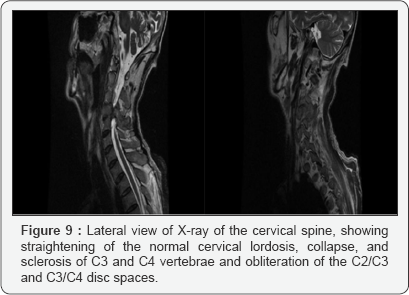

Magnetic resonance imaging

(MRI) is the criterion standard for evaluating disk-space infection and osteomyelitis of the spine and is most effective for demonstrating the extension of disease into soft tissues and the spread of tuberculous debris under the anterior and posterior longitudinal ligaments. . MRI is also the most effective imaging study for demonstrating neural compression.

• Contrast-enhanced MRI findings in Pott disease include thin and smooth enhancement of the abscess wall and a well- defined paraspinal abnormal signal.

• Thick and irregular enhancement of the abscess wall and an ill-defined paraspinal abnormal signal suggest pyogenic spondylitis.

Complications

Pott disease is the most dangerous form of musculoskeletal tuberculosis because it can cause-bone destruction, deformity, paraplegia, resulting from spinal cord compression usually respond well to chemotherapy, sometimes operative decompression is required motor deficit -a nerve is compressed Association impairment scale (ASIA) is useful to document neurological recovery from Pott disease. A designation of ASIA A indicates the most severe neurological compromise, ASIA E the least. At the beginning of treatment, most individuals are characterized as ASIAD. Late-complication can still occur reactivation of TB instability or deformity of the spine (Figures 8 & 9) [13-17].

Lab test: CBC anemia, neutropenia, lymphocitosis ESR- elevated, 72mm/hr (Westergreen method). PCR elevated -microbiology-sputum, BK direct, cultures -HIV screening negative IDR at PPD+ -QuantiFERON test + ImagisticS -X-ray chest showed reticulo-nodular shadows in both apices but worse on the left.-X-ray cervical spine showed: Straightening of the normal cervical lordosis, collapse, and sclerosis of C3 and C4 vertebrae and obliteration of the C2/C3 and C3/C4 disc spaces. Other findings include widening of the prevertebral soft tissue from C1-C5 with resultant narrowing of the adjoining airway (oropharynx and hypopharynx). There was also sclerosis of the pedicles of C3/C4 vertebrae and osteophytic spurring of the antero-superior margin of C4. Lesions of the cervical spine cause neurologic deficit more frequent because the spinal canal in this region is small relative to the diameter of the cervical cord. The mechanism of neurologic symptoms in cervical spine TB include: local inflammation, tuberculous vasculitis and ischemia, subluxation of the vertebrae, abscess on the spinal cord or nerve root, and impingement of the discs. He was admitted in the ICU for rapid respiratory failure caused by paralyzed respiratory muscles intubated and put on mechanical ventilation. Tracheostomy was another must to do procedure plus drainage of the retropharyngeal space. Even of the good coverage with antibiotics -Meropenem plus Vancomycine, plus Isoniazid, Streptomycin, Ethambutol and Ryfampin he developed a severe bronchopneumonia with multirezistant Acinetobacter -and after a long treatment including Colistine sulphat he was clean but very weak. He continue the treatment immobilized and ventilated ,he was proposed for laminectomy but he died on surgery because of extremely late presentation.